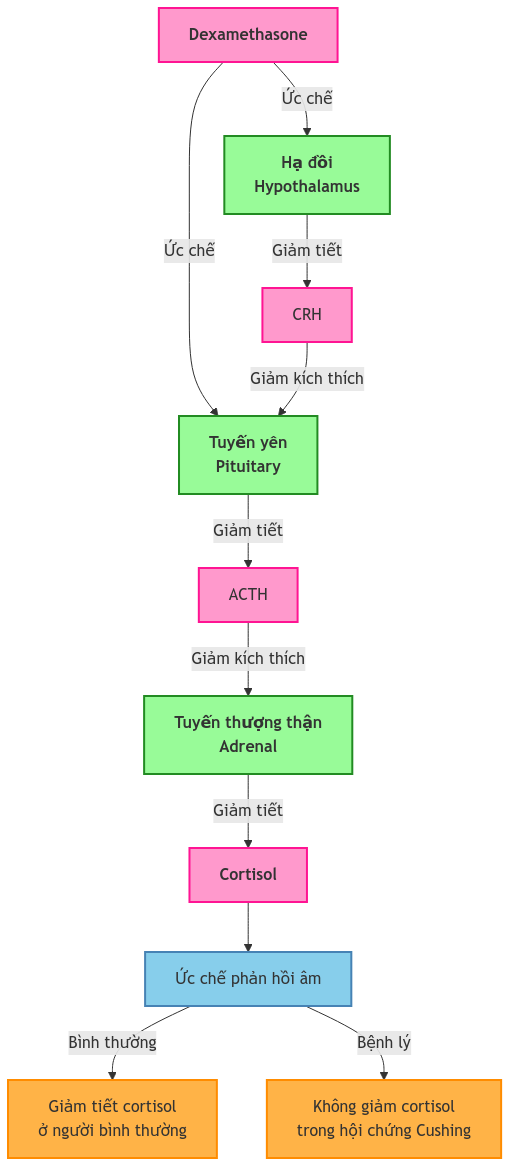

Nghiệm pháp ức chế Dexamethasone: Nguyên lý và ứng dụng lâm sàng

Nghiệm pháp ức chế Dexamethasone: Nguyên lý và ứng dụng lâm sàng

Ths. [...]